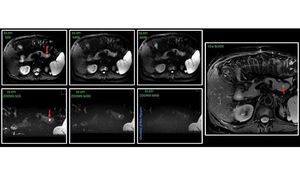

MR Abdominal Imaging – conventional Single Shot EPI (SS-EPI) vs. ZOOMit @ Prisma 3T ZOOMit SS-EPI gives you the possibility to reduced FOV with minimal blurring and higher spatial resolution compared to conventional SS-EPI. Pancreas lesion (red arrow).#s_mri #siemens #mri #zoomit #dwi